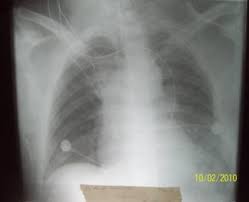

Atelectasia pulmonar posoperatoria

Se produce en los primeros días posoperatorios los signos mas importantes son elevación del diafragma, limitación de sus movimientos, disminución de los ruidos respiratorios y, a veces, unos pocos estertores en el lado afectado.

A la inspección la temperatura, pulso y respiraciones están aumentados, el paciente esta congestionado, molesto, pero no parece gravemente enfermo, percibe la presencia de moco en su garganta; a la percusión y auscultación se puede descubrir disminución del ruido respiratorio, limitación de los movimientos del diafragma y a veces pero no siempre pequeños estertores  en la base pulmonar del lado afectado.

Colapso pulmonar masivo

Un bronquio principal esta ocluido y todo el aire de un pulmón ha sido completamente resorbido, el pulmón esta mas o menos comprimido y el mediastino se halla desviado hacia el lado afectado. A la inspección presenta cianosis, disnea, gran dificultad respiratoria y dolor moderado o intenso; en la palpación la traque esta desviada hacia el lado enfermo, han desaparecido las vibraciones vocales y en el lado afectado el tórax se dilata poco o nada; la percusión da macicez, las maciceces cardiacas y mediastinica están desviadas hacia el lado afectado; la auscultación no se percibe ruido respiratorio ni se transmite la voz, a veces se oyen estertores bronquiales fuertes, el diagnostico se confirma cuando se obliga al paciente a toser con fuerza o se le somete a aspiración traqueal.